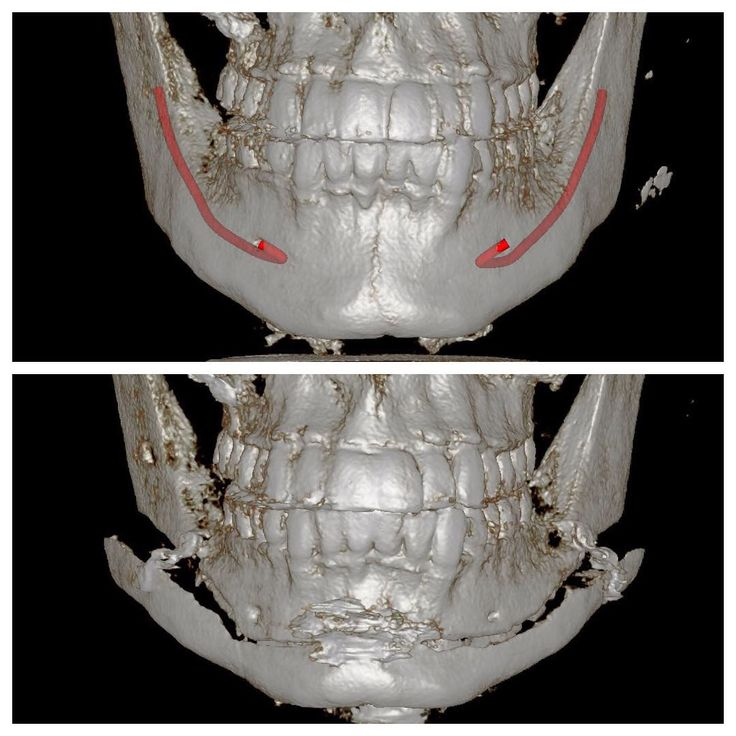

chin

chin is deviated a few mm sideways, and upturned in the side profile. would it be easier to just have the entire thing shaved off and augmented instead of doing genio? I'd get more freedom in my design and I think it's be a faster recovery.

jaw

if i do a chin implant, should I go ahead and design the implant to augment the entire mandible? fix the angle a bit and add some flare at the ends?

chin

chin is deviated a few mm sideways, and upturned in the side profile. would it be easier to just have the entire thing shaved off and augmented instead of doing genio? I'd get more freedom in my design and I think it's be a faster recovery.

jaw

if i do a chin implant, should I go ahead and design the implant to augment the entire mandible? fix the angle a bit and add some flare at the ends?